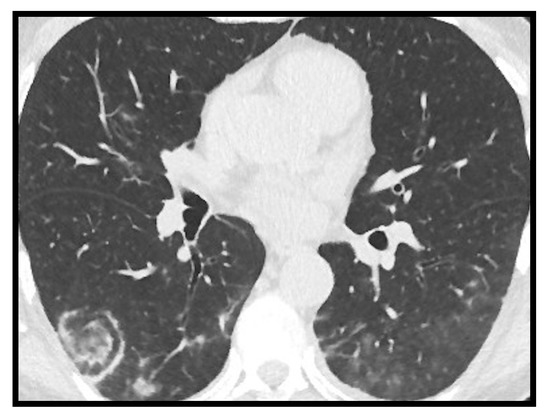

2.5. Halo Sign and Reverse Halo Sign

Halo sign consists of a shaded area of increased parenchymal density surrounded by peripheral ground glass changes. It was studied by Wu and Chen et al. [18], who discovered it in 18/130 COVID-19 patients (13%), considering it as an unusual feature associated with the initial phase of the disease. The reverse halo sign can be defined as a clearly rounded area of “ground glass-like” increased parenchymal density, circumscribed by a consolidation ring (Figure 5). It likely represents the disease progression towards consolidation as described by Bernheim et al. [19], who detected it in 4% of the patients studied at 6–12 days of infection.

Kuang et al. [20] conducted a study aimed to identify the CT differences between H1N1 influenza pneumonia and COVID-19. Their results showed that the reverse halo sign in COVID-19 pneumonia was present in 18.5% of cases, and that this sign was more common than in H1N1 influenza pneumonia (p < 0.05).

Figure 5. Reverse halo sign in right lower lobe in COVID-19.